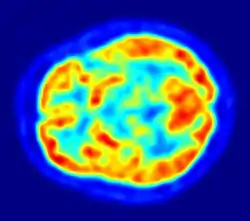

A flat oval object is surrounded by blue. The object is largely green-yellow, but contains a dark red patch at one end and a number of blue patches.

PET image of the human brain showing energy consumption

The brain consumes up to 20% of the energy used by the human body, more than any other organ.[131] In humans, blood glucose is the primary source of energy for most cells and is critical for normal function in a number of tissues, including the brain.[132] The human brain consumes approximately 60% of blood glucose in fasted, sedentary individuals.[132] Brain metabolism normally relies upon blood glucose as an energy source, but during times of low glucose (such as fasting, endurance exercise, or limited carbohydrate intake), the brain uses ketone bodies for fuel with a smaller need for glucose. The brain can also utilize lactate during exercise.[133] The brain stores glucose in the form of glycogen, albeit in significantly smaller amounts than that found in the liver or skeletal muscle.[134] Long-chain fatty acids cannot cross the blood–brain barrier, but the liver can break these down to produce ketone bodies. However, short-chain fatty acids (e.g., butyric acid, propionic acid, and acetic acid) and the medium-chain fatty acids, octanoic acid and heptanoic acid, can cross the blood–brain barrier and be metabolised by brain cells.[135][136][137]

Although the human brain represents only 2% of the body weight, it receives 15% of the cardiac output, 20% of total body oxygen consumption, and 25% of total body glucose utilization.[138] The brain mostly uses glucose for energy, and deprivation of glucose, as can happen in hypoglycemia, can result in loss of consciousness.[139] The energy consumption of the brain does not vary greatly over time, but active regions of the cortex consume somewhat more energy than inactive regions, which forms the basis for the functional neuroimaging methods of PET and fMRI.[140] These techniques provide a three-dimensional image of metabolic activity.[141] A preliminary study showed that brain metabolic requirements in humans peak at about five years old.[142]